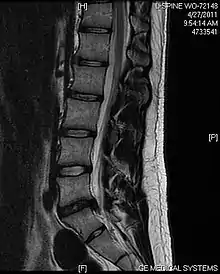

L'imagerie par résonance magnétique peut montrer la hernie, le canal vertébral, les nerfs, les tissus environnants. Les tissus mous sont les mieux analysés par cet examen qui est le plus performant pour le diagnostic de hernie discale. Les images pondérées en T2 montrent clairement la hernie.

IRM cervicale sagittale montrant une hernie discale de niveau C5-C6.

IRM cervicale sagittale montrant une hernie discale de niveau C6-C7.